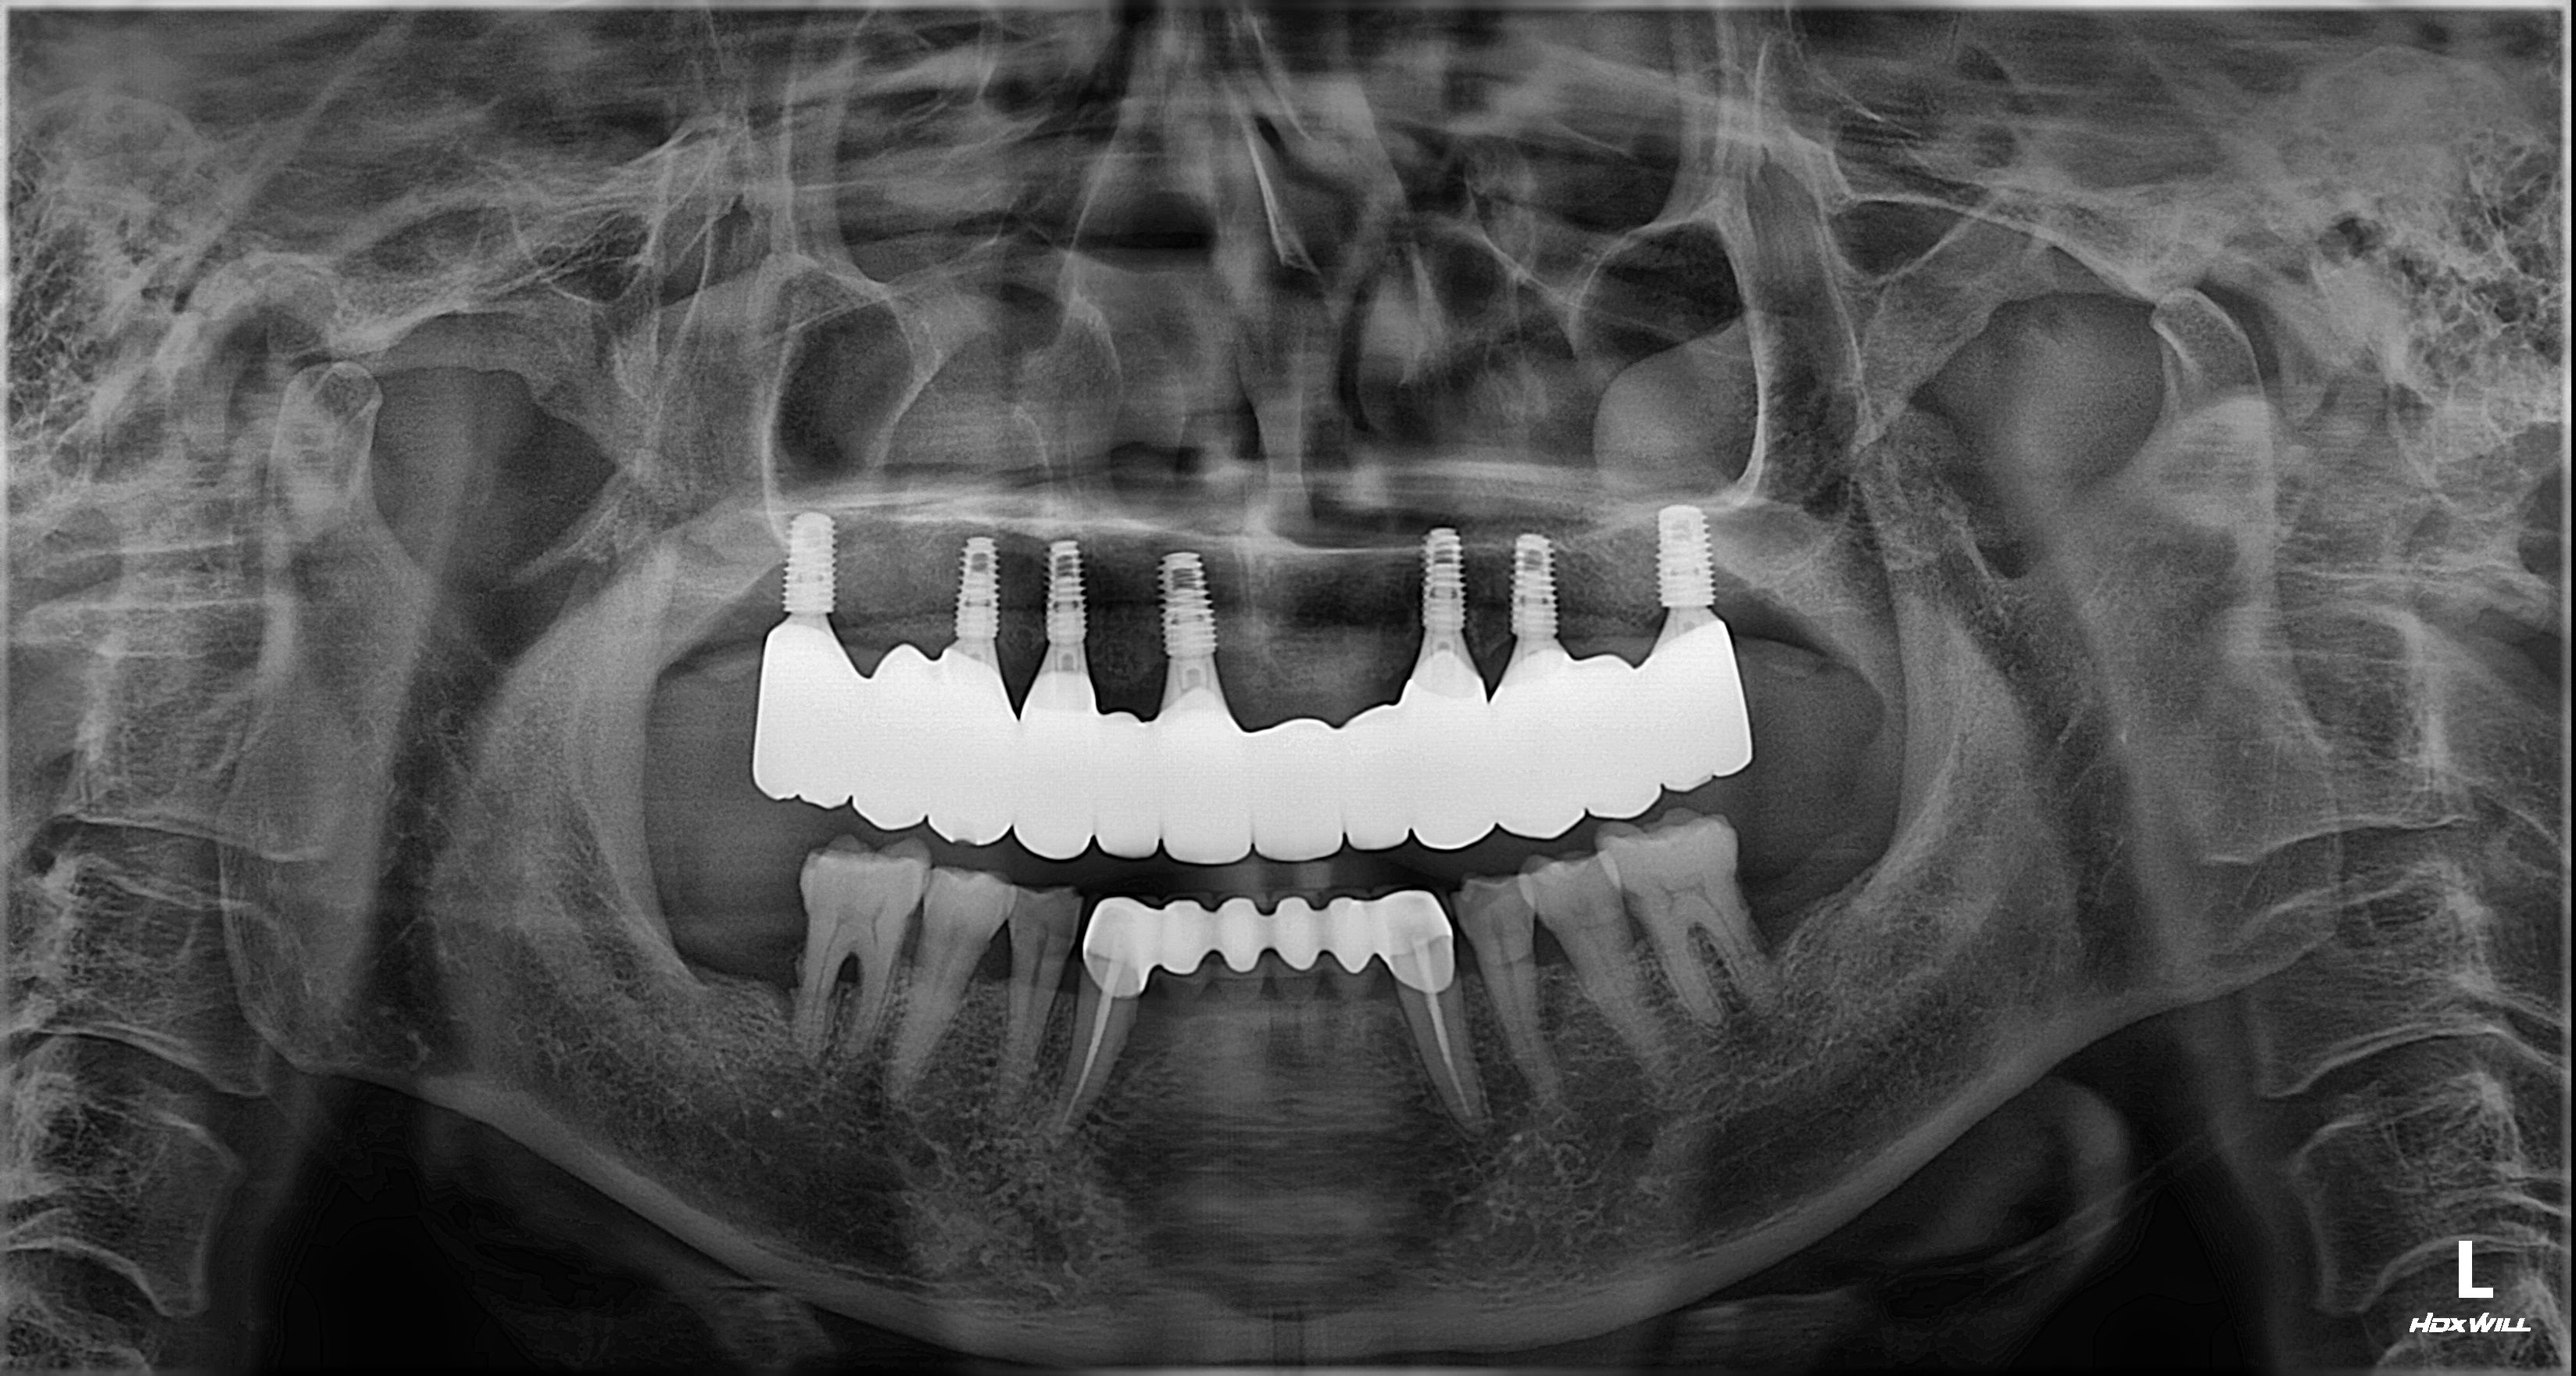

촬영일시: 2025.08.31.

촬영일시: 2026.03.10. [ 치료기간: 2025년 09월 20일 ~2026년 02월 21일 ] ※ 365서울앞선치과의원의 모든 컬럼은 각 진료과 의료진이 직접 작성합니다. 365서울앞선치과의원 임상 케이스 게시물은 환자분께 의학적으로 정확하고 상세한 정보를 드리기 위해 각 진료과 의료진이 직접 작성하며, 모든 증례 사진은 본원 의료진이 직접 시술한 증례를 촬영한 것으로, 의료법 제23조, 제56조에 의거하며 환자분의 동의를 얻어 포스팅에 사용하였습니다. 또한 해당 케이스는 본 환자분의 치료 결과이며, 환자 상태에 따라 치료의 결과는 달라질 수 있습니다. |